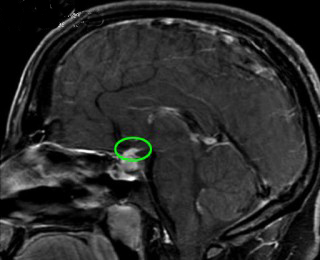

本病的病因尚未完全阐明。由于病理上垂体有明显的淋巴细胞浸润,部分病人血中可检出抗垂体抗体,故目前认为本病可能因自身免疫所致。但是,抗垂体抗体的检出率并不高。晚近,桥本等分析1962~1995年间文献中报道的124例淋巴细胞性腺垂体炎(其中100例经病理证实),发现只有7例抗垂体抗体阳性,抗垂体抗体阳性率较低与所用检测方法(免疫荧光法)不够敏感有关。此外,不少病人同时存在其他内分泌腺的自身免疫性炎症,这也支持本病系自身免疫所致的观点。

在本病的发病机制尚不清楚。据文献分析,多数作者认为是一种自身免疫疾病。由于妇女在妊娠期垂体会增生肥大,产后垂体慢慢缩小,释放了大量垂体抗原,促使产生自身免疫反应,淋巴细胞浸润垂体;引起垂体组织破坏。另外,Vanneste曾报道1例49岁妇女,在患病毒性脑膜炎后,发生垂体功能低下,1年后手术证实为淋巴细直接感染垂体引起的。本病有许多病历与其他免疫病同时发生,很有可能与遗传因素有关。